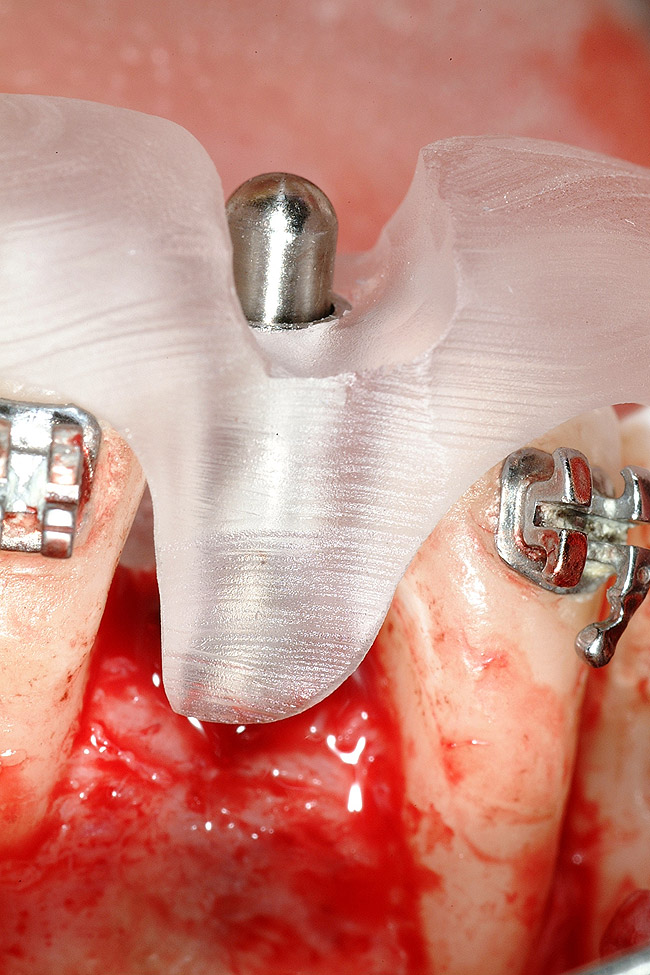

Figure 17  Tooth-supported SurgiGuide (Materialise Dental, Leuven, Belgium) (2-mm level) in place.

Figure 17